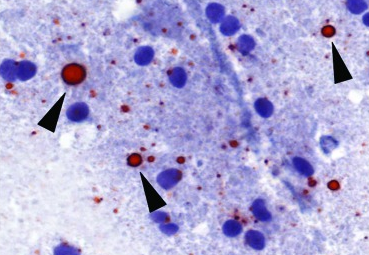

Direct rapid immunohistochemical test (DRIT)

The DRIT for rabies functions similarly to the DFA test in detecting the presence of rabies virus antigen in animal tissues. Like DFA, DRIT relies on observing rabies virus-expressed proteins in infected nervous system tissues.

- Brain tissue is ideal due to its high concentration of rabies antigen.

- Other innervated tissues may have antigens, but they are less accurate at detecting rabies when compared to brain tissues.

- The key component of the DRIT test is rapid immunohistochemical staining with anti-rabies antibodies.

- These antibodies are labeled with a chromogenic marker and when incubated with suspect tissue, the marker binds specifically to rabies antigen.

- Excess antibodies are then washed away, and areas containing rabies antigens appear in color under a light microscope.

- The absence of staining indicates the absence of rabies virus

Like DFA, DRIT boasts high sensitivity and specificity. It has been thoroughly evaluated by international, national, and state health laboratories.